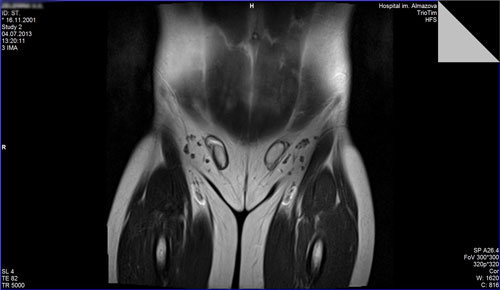

Синдром Рокитанского-Кюстнера-Майера-Хаузера у девочки 16 лет с первичной аменореей. МРТ органов малого таза. (агенезия матки, влагалища, тазовая дистопия единственной почки).